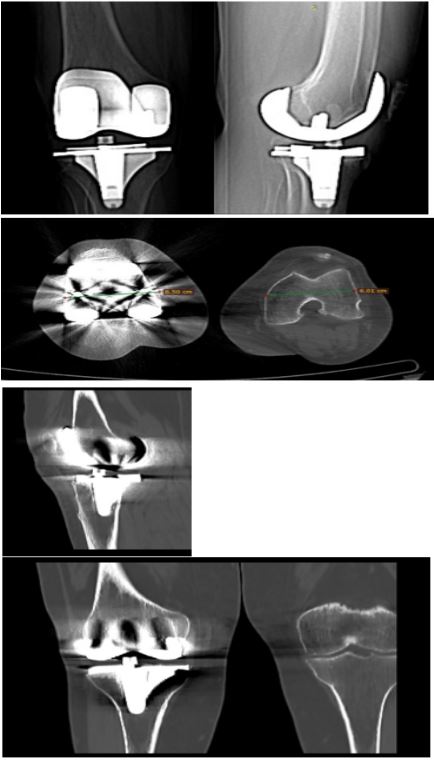

Figure 1 and 2: Pre-operative implants XR and CT scan.

Figure 3: Intra-operative mapping directly on the current implants.

Figure 4: Post-operative mapping directly on the current implants.

Figure 5: Post-operative implants XR.

The knee was tight in flexion and somewhat loose in extension. After removing the 9 mm polyethylene, femoral and tibial checkpoints, along with CORI array pins, were secured. Real-time intra-operative gap balance and a 3D model of the rTKA were planned. The femoral and tibial components were carefully removed, without significant bone loss. The patellar button was well-fixed and left intact.

Using the operative plan, the CORI robotic arm with a saw attachment made minimal fresh cuts to the femur and tibia. Trial components were implanted, resulting in a well-balanced knee with a 13 mm trial polyethylene insert. Osteophytes around the patella were removed and the joint was irrigated. Femoral and tibial components were cemented and implanted (femur size 4 PS, femoral stem 12 mm X 120 mm, tibial size 2, tibial stem 10 mm X 120 mm), with a 13 mm polyethylene PS insert. Intra-operative tests showed smooth and centered patellar tracking, with knee ROM ranging from -5 to 110 degrees. The operative time was 172 min, a significant increase as compared with our standard (96±23 minutes).

Following the surgery, she embarked on a three-week rehabilitation program at our institution’s Rehabilitation Department, commencing five days post-surgery, and achieved a Range of Motion (ROM) of 0-95°.

At the latest follow-up, she could ambulate without assistance, with knee ROM of 0-100 degrees and slightly less strength compared to the other leg.